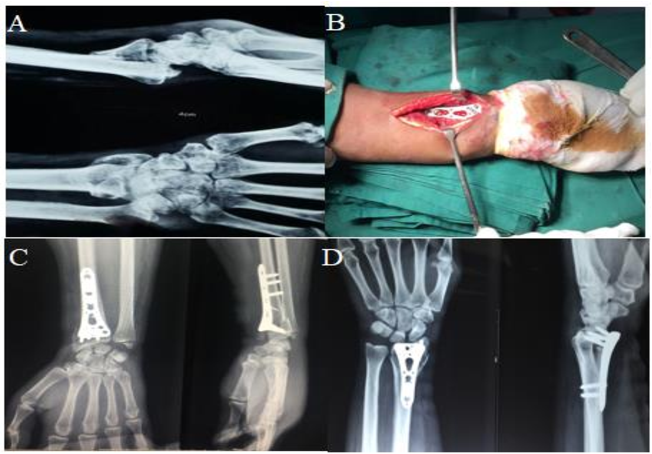

Во время операции перелом обнажается, и костные фрагменты возвращаются в правильное положение. Стопорная шайба затем располагают над местом перелома, и через пластину в кость вводят винты для стабилизации перелома.После надежной фиксации перелома разрез закрывается, и начинается процесс восстановления.

Стопорная шайба хирургия включает использование металлических пластин со специальными отверстиями для винтов, которые фиксируют винты на месте.Эти пластины предназначены для обеспечения стабильной фиксации и равномерного распределения нагрузки по сломанной кости.Винты, используемые в хирургии блокирующей пластины, ввинчиваются в пластину, создавая конструкцию с фиксированным углом, способную выдерживать значительные нагрузки.

Хирургия запирающей пластины предлагает несколько преимуществ при лечении сложных переломов.К ним относятся стабильная фиксация, ранняя мобилизация, улучшенное выравнивание, снижение риска неправильного сращения и улучшение результатов заживления.Жесткая конструкция, обеспечиваемая стопорные пластины обеспечивает немедленную нагрузку и лучшее функциональное восстановление.